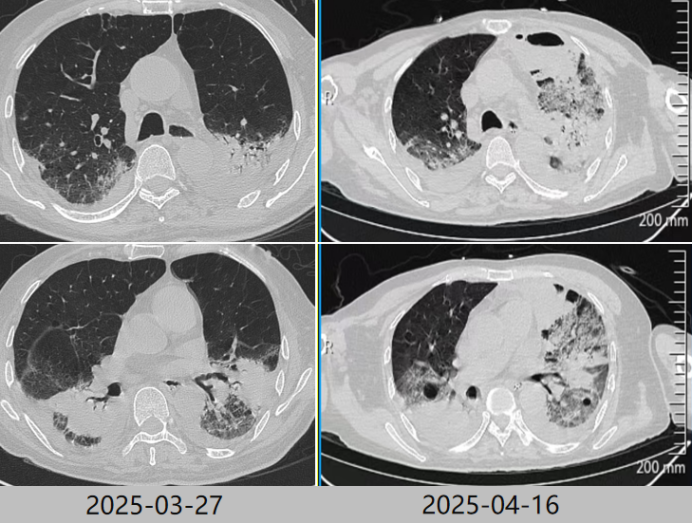

5. 患者治疗期间氧合情况

患者在我院住院治疗期间氧合指数变化如图6所示。

图片

6  患者治疗期间氧合指数变化情况